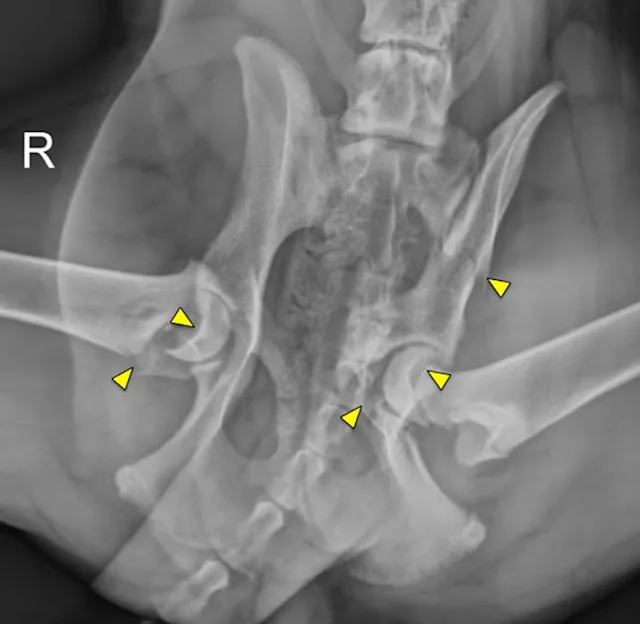

VD and lateral x-rays of dog’s pelvis showing orthopedic wires within the proximal aspect of the right femur.